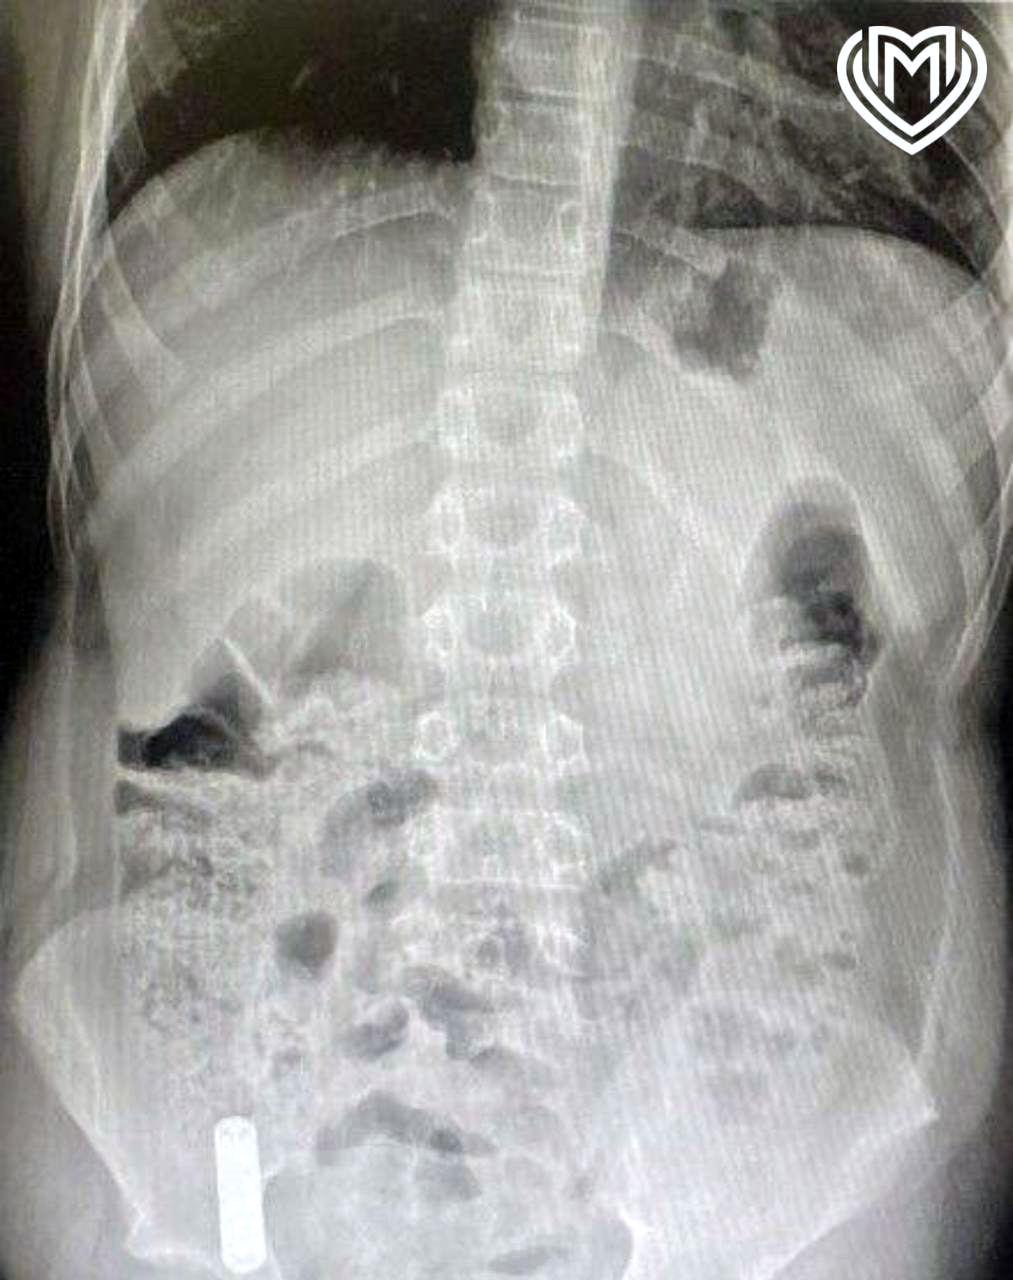

В медучреждение 12-летнего пациента привезли родители. Они рассказали, что сын проглотил батарейку из пульта от телевизора. Между моментом инцидента и обращением за помощью прошло очень мало времени. За это время инородное тело успело опуститься в слепую кишку. Врачи приняли решение о немедленном извлечении предмета.

«Вначале выполнили лапароскопию, чтобы визуализировать как возможные осложнения, так и расположение инородного предмета. Затем провели эндоскопическое исследование, во время которого с помощью специальной петли извлекли литиевую батарейку», — поделился детский хирург, заведующий хирургическим отделением №1 Игорь Хворостов.

Врач добавил, что батарейка не успела окислиться, так что химического ожога удалось избежать. Мальчика выписали домой через два дня, как подчеркнули специалисты, полностью здоровым.